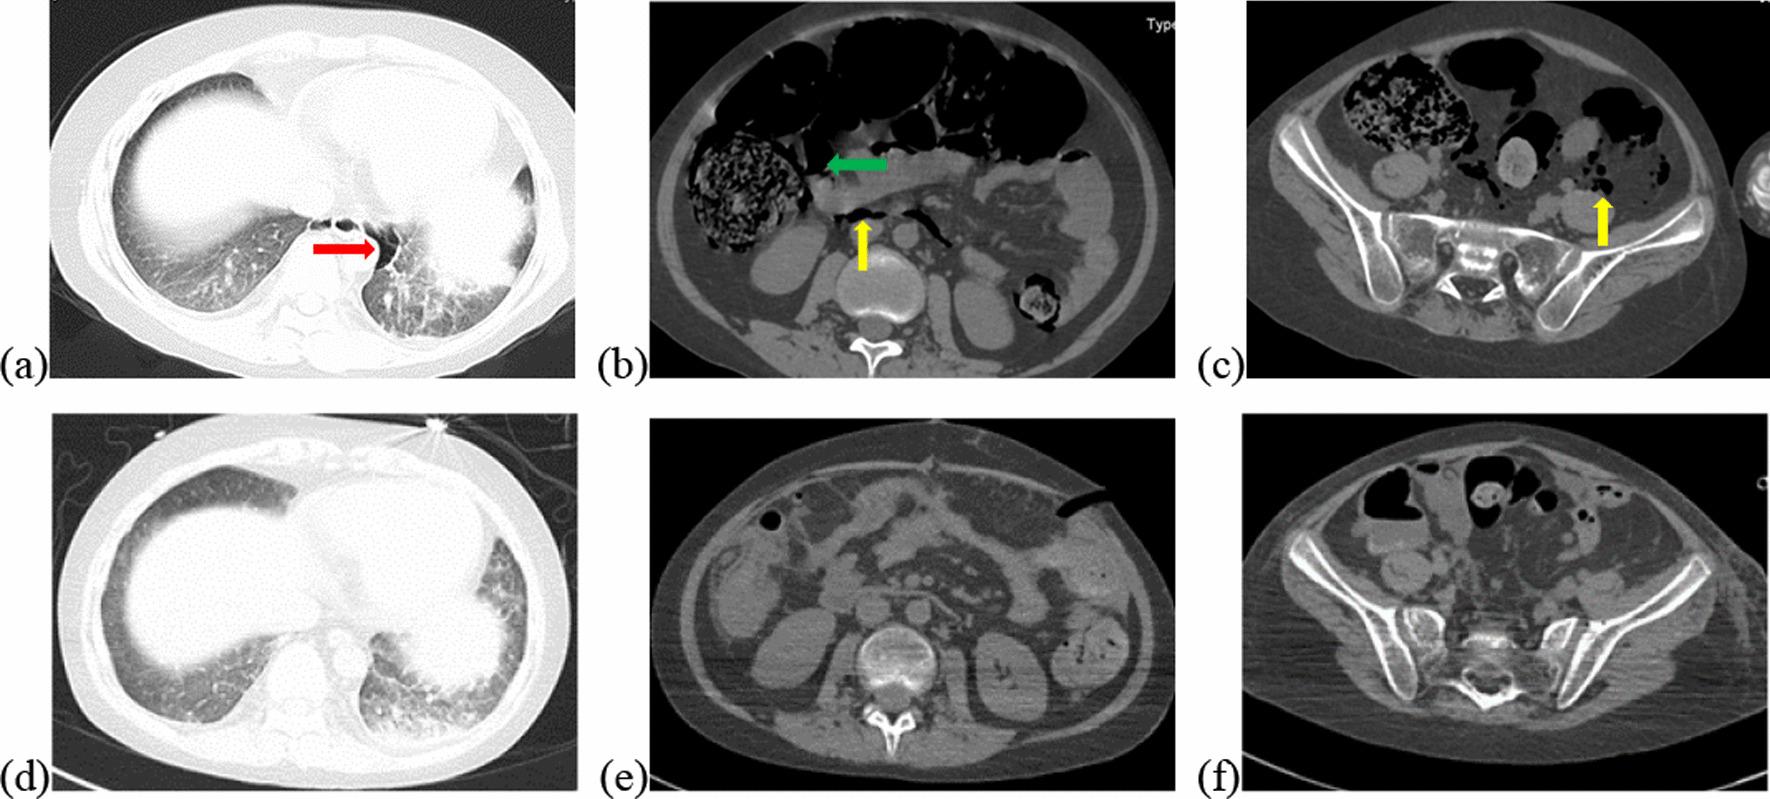

Pneumatosis cystoides intestinalis (PCI) is a rare condition characterized by the presence of air collection within the subserosa and/or submucosa of the gastrointestinal wall. Due to the lack of specific symptoms, PCI is likely to be misdiagnosed or missed without the use of imaging techniques or gastrointestinal endoscopy. Here, we report a patient who complained of abdominal distention and constipation after chemotherapy for hematological malignancies, and was diagnosed with secondary PCI via computed tomography (CT) and exploratory laparotomy. Pneumoperitoneum was no longer observed after two weeks of conservative treatments. Notably, the possibility of intra-abdominal pressure (IAP) as a predictor for surgical intervention was proposed. Furthermore, we conducted a literature review on PCI after chemotherapy in hematological malignancies to raise awareness of etoposide-related PCI, while whether PCI could be identified as an adverse event of etoposide requires more evidence.

肠气肿(PCI)是一种罕见的疾病,其特征是胃肠道壁的浆膜下和/或黏膜下有空气积聚。由于缺乏特定的症状,如果不使用影像学技术或胃肠内窥镜检查,PCI 很可能被误诊或漏诊。在这里,我们报告了一例患者,他在血液恶性肿瘤的化疗后出现腹胀和便秘,并通过计算机断层扫描(CT)和剖腹探查术诊断为继发性 PCI。经过两周的保守治疗后,气腹不再观察到。值得注意的是,提出了腹腔内压(IAP)作为手术干预预测因素的可能性。此外,我们对血液恶性肿瘤化疗后 PCI 进行了文献回顾,以提高对依托泊苷相关 PCI 的认识,而 PCI 是否可以被确定为依托泊苷的不良事件还需要更多的证据。